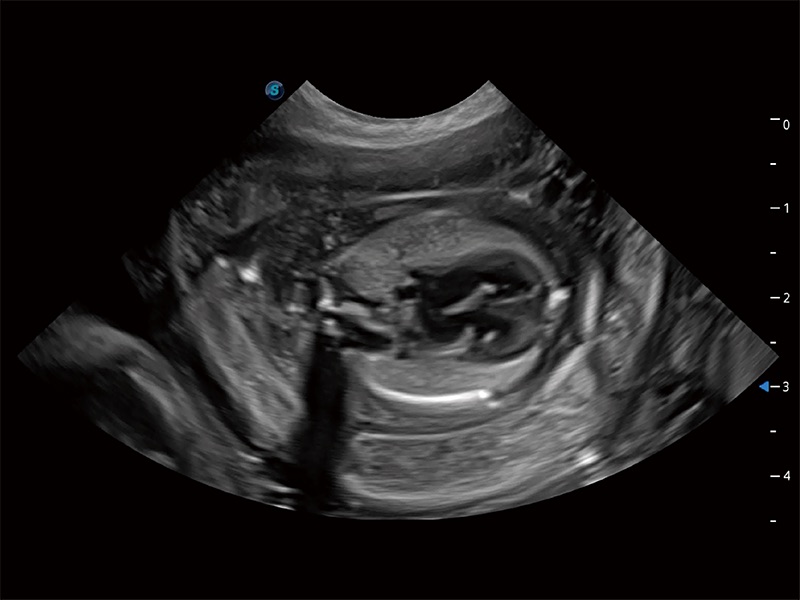

动物是人类最亲密的朋友和最值得信赖的伙伴。美狮贵宾会官网也一直致力于探索动物专用的超声影像解决方案。全新推出的ProPet系列,是美狮贵宾会官网在动物超声影像智能化、专业化、精准化的一次跨越式革新。动物不能用言语来表述自己的不适,通过超声影像,ProPet系列搭建了动物医生与不同物种沟通的“桥梁”,为动物医生注入了“治愈之力”。 ProPet 80 是美狮贵宾会官网匠心打造的一款高端动物专用彩超,采用性能卓越的全新硬件架构,极大提升超声系统的运行效率和数据处理能力,帮助动物医生从容应对日益增多的挑战性病例和日益多样化的临床需求。

高性能和先进的临床应用工具可以为动物医生提供临床信心。ProPet 80 搭载了先进的腹部和浅表应用工具,帮助医生在日常临床实践中发挥前所未有的作用。

ProPet 80 专为动物医生设计,对不同的动物体型和生理结构作出了针对性的优化。通过动物影像专用软件,可满足个性化的应用需求,帮助动物医生获得更精确的诊断数据。

为精细结构及组织边缘提供高清晰度的图像和更大的成像视野。帮助减轻医生的用眼疲劳,快速精准获得测量的数据。